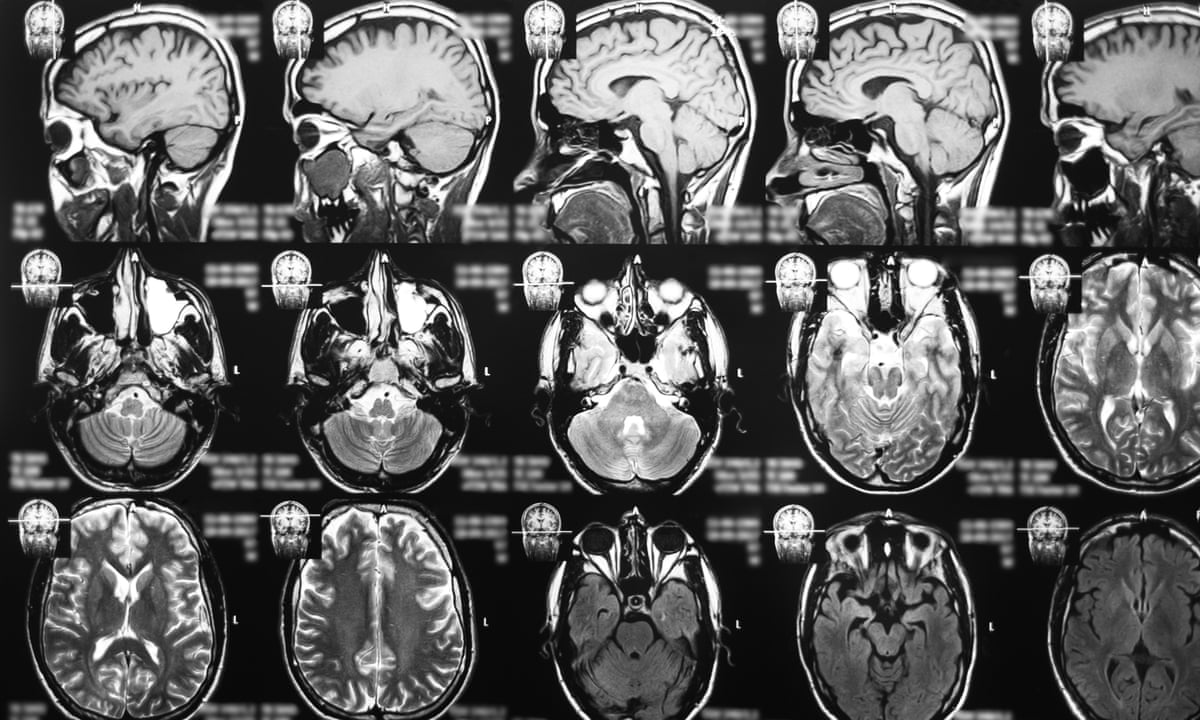

Brain cancer is divided into four progressive and overlapping stages. Based on the signs and symptoms in the last days before death in patients with glioblastoma supportive drug treatment remains challenging. How Long Does End Stage Glioblastoma Last.

Due to a decrease in level of consciousness and cognitive impairment assessment of clinical signs and symptoms such as headache at the end of life is difficult. How Long Does End Stage Glioblastoma Last. When the body is passing it will conserve energy.

Cancers Free Full Text Differentiating Glioblastomas From Solitary Brain Metastases An Update On The Current Literature Of Advanced Imaging Modalities Html